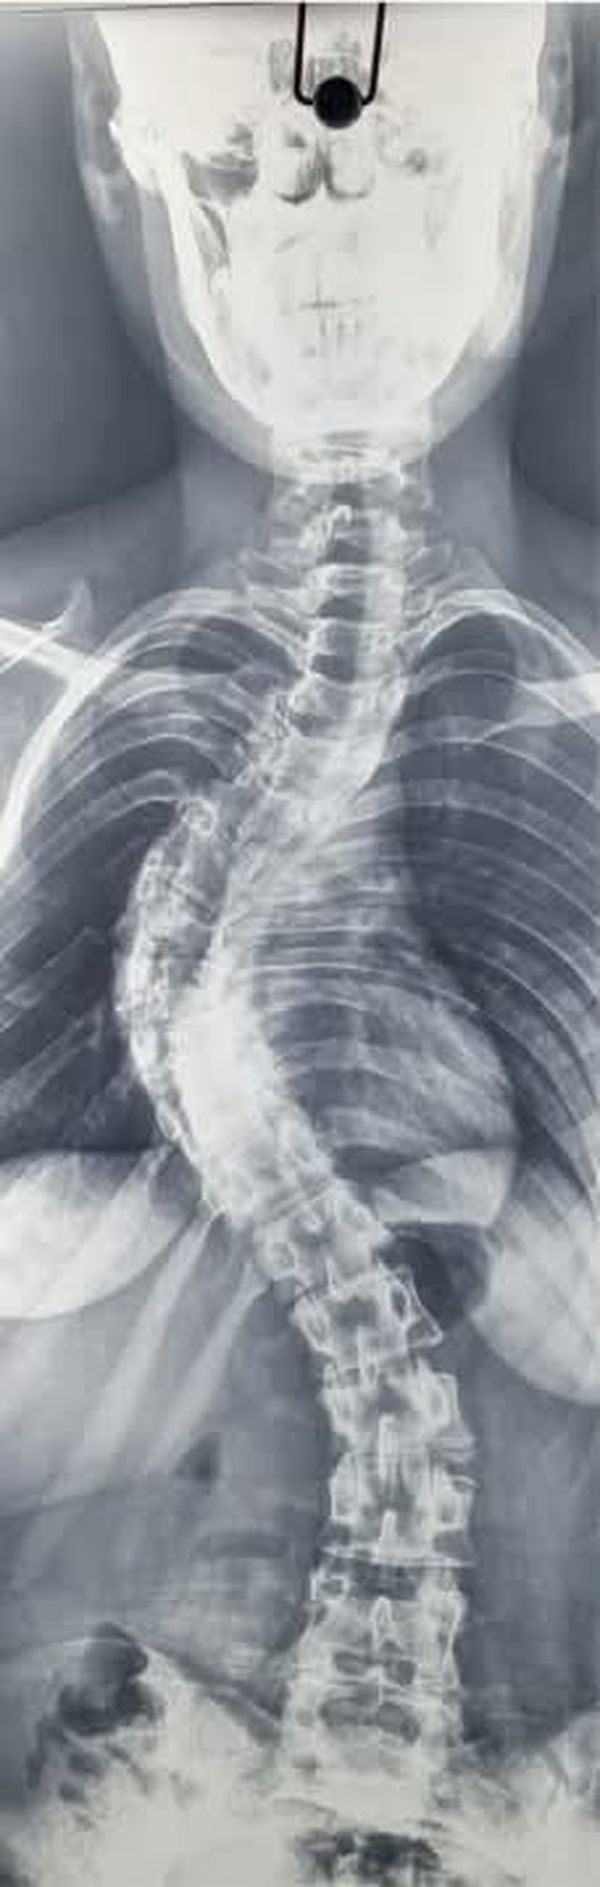

انت تتابع الان خبر فريق طبي بجامعة بني سويف ينجح في إصلاح اعوجاج بالعمود الفقري لأحد المرضى حصرياً والان نترككم مع التفاصيل

عدن - هند جمال - أعلن الدكتور طارق على ، القائم بأعمال رئيس جامعة بني سويف، نجاح فريق طبي بقسم جراحة المخ والأعصاب بكلية الطب في إصلاح اعوجاج في العمود الفقري لأحد المرضى، وهو ما يُعد علامة بارزة في مسيرة القسم نحو تقديم خدمة طبية متقدمة، وذلك تحت إشراف الدكتور هاني حامد عميد كلية الطب، والدكتور عماد البنا المدير التنفيذي للمستشفيات.

جانب من العملية الجراحية

وأوضح رئيس جامعة بنى سويف، أن الفريق الطبي الذى أجرى العملية الجراحية إصلاح اعوجاج في العمود الفقري لأحد المرضي، ضم الدكتور محمد شعبان محمود، أستاذ ورئيس القسم، والدكتور عبدالرحمن صابر المسؤول عن متابعة جراحات اعوجاج العمود الفقري، وبمشاركة كل من الدكتور مصطفى فكري و الدكتور محمود رمضان.

و هنأ رئيس الجامعة الفريق الطبي على هذا الإنجاز الطبي المتميز، الذي يُعد نموذجًا مشرفًا لما يمكن أن تقدمه الكفاءات الجامعية من خدمات صحية متقدمة، لافتاً إلى أن إجراء هذا النوع من العمليات التدقيقية يعكس مستوى التطور الذي وصلت إليه المستشفى الجامعي من حيث الإمكانيات البشرية والتقنية، مؤكدا حرص الجامعة الدائم على دعم كل الجهود التي تساعد في رفع جودة الخدمات المقدمة للمواطنين.